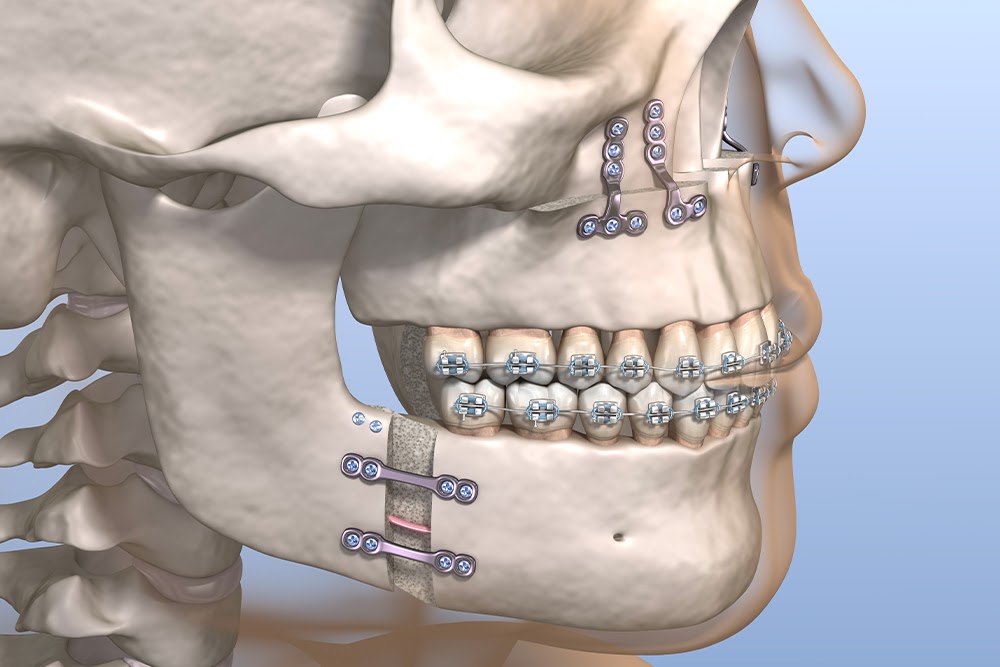

La CCL propose une offre chirurgicale complète — orthopédie, chirurgie générale, vasculaire et neurochirurgie — avec un suivi rigoureux et une équipe dédiée à votre rétablissement.

Chaque spécialité est assurée par des chirurgiens expérimentés avec un protocole de soins rigoureux.